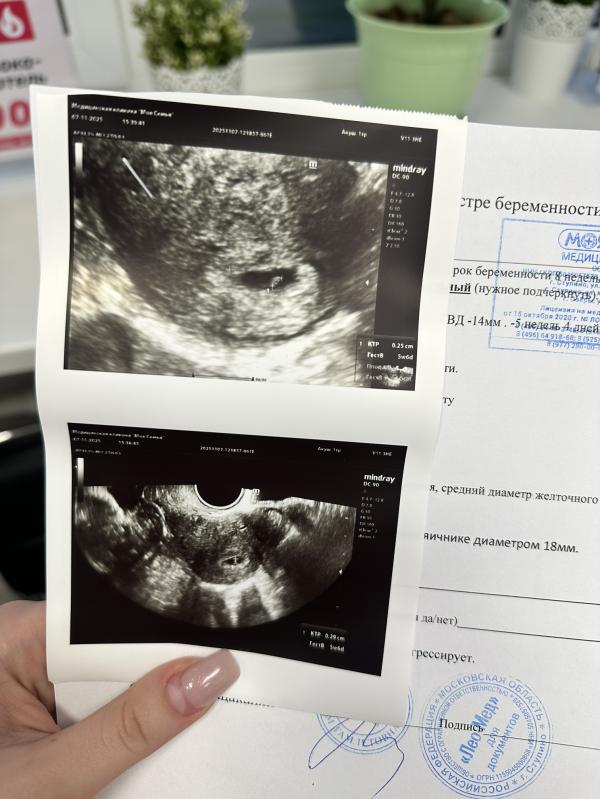

Первое УЗИ на 6 неделе беременности: фото и эмоции

А вот и наше узи🙏🏼

Завтра ровно 6 неделек🥰

Да, но пока еле слышно

Сколько ктр?

0,29мм